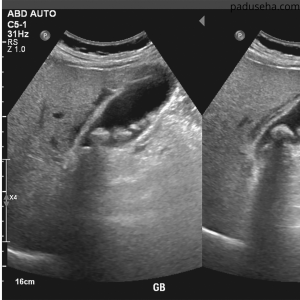

Batu empedu sering kali tidak menimbulkan gejala pada awalnya. Namun, ketika batu mulai menyumbat saluran empedu, kondisi ini dapat berubah menjadi serius. Jika batu empedu tidak diobati, berbagai risiko jangka panjang dapat muncul dan mengganggu kesehatan secara keseluruhan. Karena itu, memahami bahaya yang mungkin terjadi sangat penting untuk mencegah komplikasi yang lebih berat.